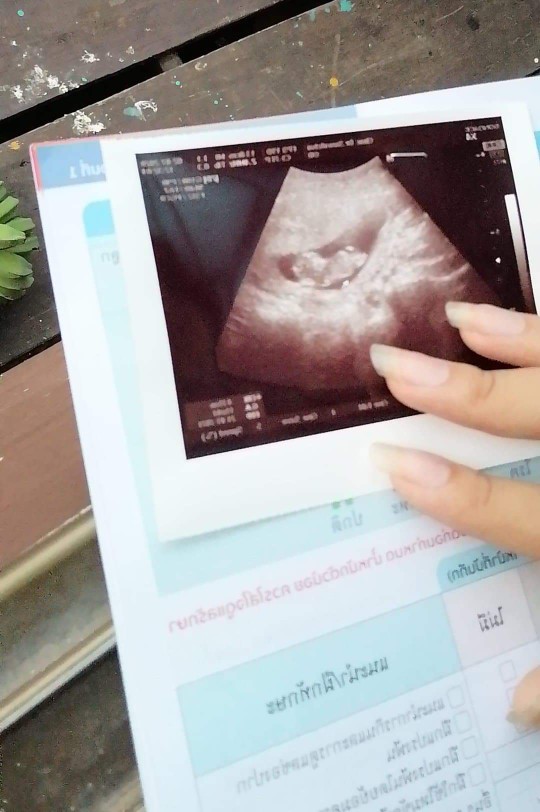

บ้านนี้ตอน10วิค1วันค่ะ 😄

ประมานนี้เหมือนกัน

บ้านนี้10สัปดาห์คะ